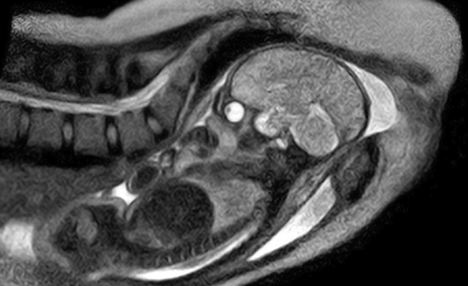

德國醫(yī)院實(shí)現(xiàn)醫(yī)學(xué)突破獲得嬰兒降生時(shí)的圖片

據(jù)英國《每日郵報(bào)》12月7日?qǐng)?bào)道,德國柏林沙里特醫(yī)院近日實(shí)現(xiàn)了一項(xiàng)醫(yī)學(xué)突破,他們利用核磁共振掃描在全球首次獲得嬰兒降生過程的圖像。

這些圖像是在一個(gè)德國孕婦同意在核磁共振掃描儀里分娩后拍攝到的,它能夠?yàn)榉置溥^程提供一些有價(jià)值的新的認(rèn)識(shí),也可用于在將來拯救生命。

沙特林醫(yī)院的婦產(chǎn)科醫(yī)生恩斯特·拜茵德(音譯:Ernst Beinder)表示,該孕婦的整個(gè)分娩過程都很正常,機(jī)器拍下了孕婦子宮內(nèi)的所有運(yùn)動(dòng)和整個(gè)分娩過程。“我們現(xiàn)在可以看到以前只能通過探針觀察到的全部細(xì)節(jié),這些迷人的圖片再次證明了每個(gè)分娩都是一個(gè)小奇跡,”他說。

沙特林醫(yī)院研究團(tuán)隊(duì)兩年前開始這項(xiàng)研究,本周終于取得成功。他們稱多名孕婦曾自愿參加這項(xiàng)實(shí)驗(yàn),另外還有5個(gè)孕婦的分娩過程將會(huì)被核磁共振掃描儀拍攝下來。醫(yī)院研究團(tuán)隊(duì)為此還改進(jìn)了通用的管狀核磁共振成像掃描儀,專門研制了一種特別的“開放式”掃描儀,以便為助產(chǎn)士和孕婦提供足夠的空間。

嬰兒出生過程的核磁共振成像圖片對(duì)于了解分娩并發(fā)癥至關(guān)重要,并能對(duì)大約15%需要接受剖腹產(chǎn)手術(shù)的孕婦的治療方案提供重要幫助。利用強(qiáng)大的磁體,核磁共振掃描儀能夠產(chǎn)生一個(gè)強(qiáng)大磁場,使無線電波探測到人體內(nèi)的某些原子。研究人員則可用這些數(shù)據(jù)制作出患者身體的橫截面圖,提供軟組織和骨結(jié)構(gòu)的細(xì)節(jié)。

核磁共振掃描儀被認(rèn)為比X射線更安全,但因?yàn)樗ぷ鲿r(shí)總是發(fā)出嘈雜的嗡嗡聲,很多患者不喜歡這種設(shè)備。為了保護(hù)本周參加實(shí)驗(yàn)的這位孕婦的健康,工作人員特意讓她戴上了耳套,當(dāng)孕婦體內(nèi)的羊膜囊破開后,因擔(dān)心嬰兒的聽力受損,掃描儀就被關(guān)閉了。